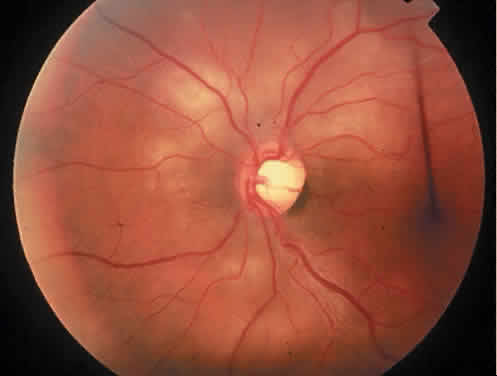

The most common ocular manifestations of TTP include papilledema, extraocular muscle palsies, and visual field defects, which usually are secondary to concomitant CNS involvement.75 Retinal findings consist of hemorrhages, retinal vascular occlusions, and serous detachments76,77 (Figs. 8 to 10). The cause of the serous detachments appears to be focal occlusion of the choriocapillaris resulting in retinal pigment epithelial damage and blood-retinal barrier disruption.76,77 Findings on fluorescein angiography are characterized by focal areas of nonperfusion of the choriocapillaris associated with late leakage into the subretinal space76 (Fig. 11). This is consistent with histopathologic studies that show occlusion of the choriocapillaris and large choroidal vessels, presumably by fibrin, with overlying necrosis of thepigment epithelium.75,76 TTP also has been linked in one case report with Purtscher retinopathy.78

Fig. 10. A 42-year-old woman with thrombotic thrombocytopenic purpura and neurosensory retinal detachments. (Courtesy of Jerry Neuwirth, MD.)

Fig. 11. Fluorescein angiogram of patient with thrombotic thrombocyto-penic purpura showing late choroidalhyperfluorescence caused by focal areas of choriocapillaris nonperfusion. (Courtesy of Jerry Neuwirth, MD.)

Clinically, the development of serous retinal detachments usually is associated with exacerbations of TTP and the development of acute hypertension. Although serous retinal detachments have been described as a preterminal event, resolution of the detachments with subsequent pigment epithelial changes may occur when the underlying hypertension and thrombocytopenia are controlled.77